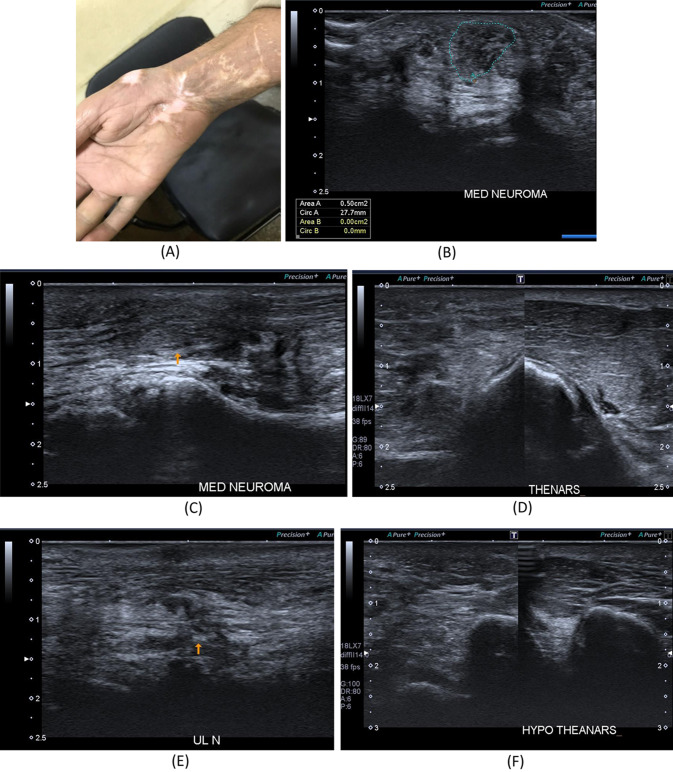

26-year- old female with a history of right distal radial fracture in July 2021 treated, After the cast removal, numbness and tingling along the radial aspect of the palm with loss of sensation of the middle finger and newly developed progressive increased thenar swelling. A Patient’s hand with prominent swelling of the thenar eminence and mid-palmar incision scar. B B-mode image, transverse axis, reveals loss of normal sonographic appearance of the left median nerve at the carpal tunnel with related hypoechoic superficial scar tissue, suggesting partial nerve injury. C Color Doppler mode image reveals pseudo-aneurysm; Pepsi sign with an area of luminal thrombosis. D The B-mode image of the thenar muscles, increased echogenicity of the left thenar muscles as compared to the right side with rather preserved girth. E Intraoperative image revealed complete injury of two of the sensory branches of the median nerve

A 25-year- old male patient presenting with history of left wrist compression/degloving injury in 2020. He underwent tendon repair surgery. A Patient’s hand. B B-mode image, transverse axis, reveals thick hypoechoic swelling of the left median nerve with loss of fascicular architecture. C B-mode image, longitudinal axis, thickened, hypoechoic focal area with loss of fascicular architecture of the median nerve at the site of injury. D B-mode image of the thenar muscles, reveal loss of normal sonographic appearance of the left side muscles with increased echogenicity as compared to the right side. E B-mode image, longitudinal axis, shows discontinuous, disorganized left ulnar nerve at the distal forearm with related hypoechoic scar tissue formation. F B-mode image of the hypothenar muscles, reveal loss of normal sonographic appearance of the left side muscles with increased echogenicity as compared to the right side